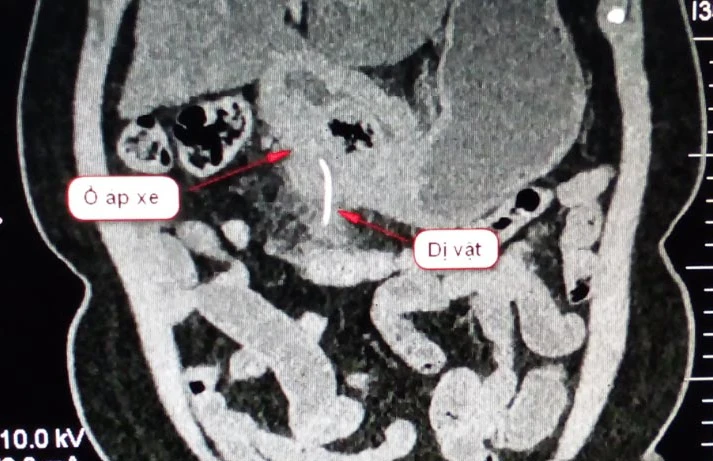

Sau khi thực hiện kỹ thuật cận lâm sàng, các BS phát hiện có dị vật cản quang trong thành dạ dày vùng môn vị. Chưa hết, các BS còn ghi nhận có dấu hiệu nghi áp xe thành dạ dày vùng hang môn vị.

Xương cá nằm trong bụng bà T. Ảnh: NGỌC DIỄM

Bà T. được các BS chỉ định phẫu thuật cấp cứu. Sau khi mở bụng, các BS tách mặt sau hang vị ra khỏi mạc treo đại tràng ngang và lấy ra xương cá dài 5 cm. Tiếp theo, các BS tiến hành khoét bỏ ổ loét viêm đường kính 3 cm rồi khâu lại dạ dày.